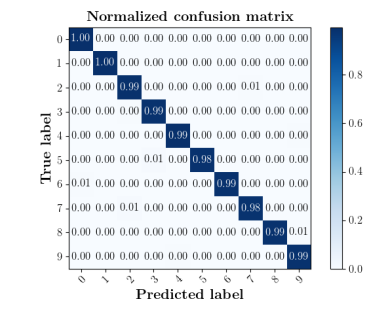

The confusion matrices in Fig. 8(b) show the effectiveness of unlabeled data in the proposed method. The classification accuracy of Femur and Lips in MIDNet improves when using unlabeled data.

We further compare the performance of MIDNet in a semi-supervised setting and a fully-supervised setting. Here, the semi-supervised setting utilizes the training data containing labeled data and unlabeled data, while the fully supervised setting only uses the labeled data. The confusion matrix in Fig. 14 shows the effectiveness of unlabeled data in our proposed method, for example, the classification accuracy of greatly improves when integrating unlabeled data (semi-supervised).